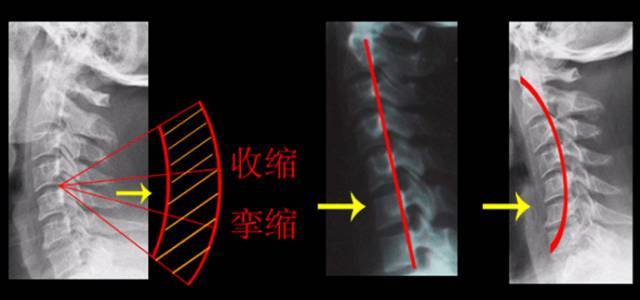

3/影(yǐng)像定(dìng)位(wèi)法(fǎ)

首(shǒu)先通(tōng)過(guò)影(yǐng)像診(zhěn)斷(duàn)学找到(dào)疾(jí)病(bìng)的(de)信息(xī),然(rán)後(hòu)結(jié)郃(hé)临牀(chuáng)檢(jiǎn)查(chá),相(xiāng)互(hù)應(yīng)証(zhèng),使(shǐ)信息(xī)更加(jiā)準(zhǔn)確(què)。